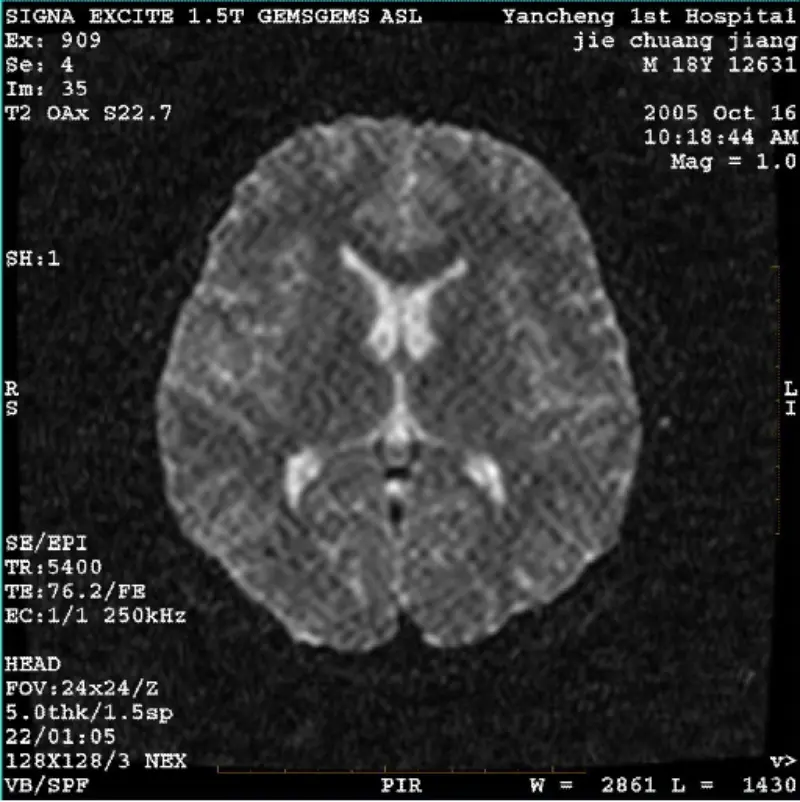

Ары қарай оқуЖҮЙЕ: 1,5T Signa Twin Excite II (бағдарламалық құрал нұсқасы 11.0M4) МӘСЕЛЕ/СИПТО DWI (масштабтау режимі және тұтас режим) және fiesta (масштабтау режимі және бүкіл режим) кескіні бар дене катушкасын немесе басын пайдаланғанына қарамастан көзге көрінетін тор немесе кордюр артефакті катушка, б......